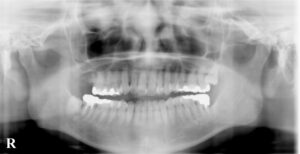

2020年6月 右上第一大臼歯の問題をご本人が訴え

レントゲンを撮影し以前と比較説明してから

2020年~2024年まで来院されなくなりました。

レントゲンでは神経の詰め物の状態の違い→

歯根の崩壊度は経時的なもの?→